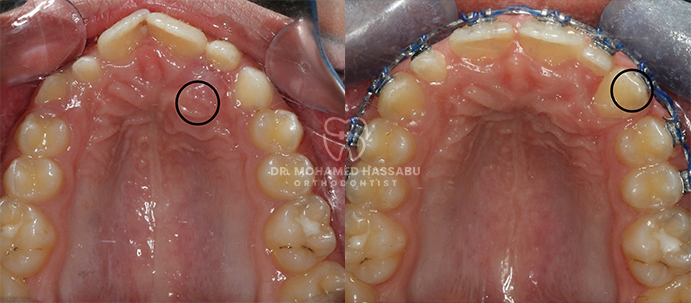

Specialized Braces:

We offer a range of specialized braces that are designed to be comfortable and effective. Our team of Orthodontists in Dubai will explain the different types of available braces and recommend the most suitable option for your child.

Throughout the braces treatment, we will provide ongoing support and monitor your child’s progress regularly. We encourage open communication with parents and caregivers to address any concerns or adjustments needed during the process.